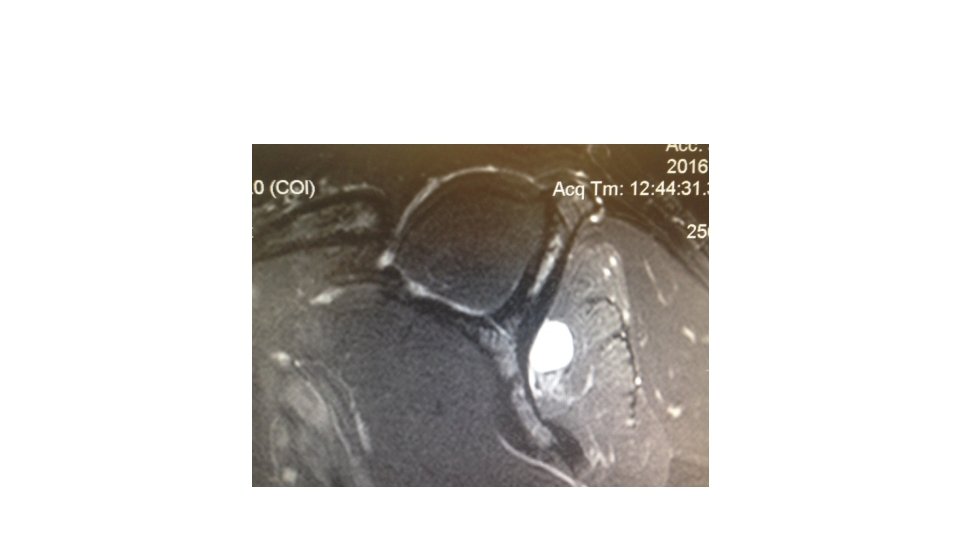

Disposition • The patient was scheduled for MRI